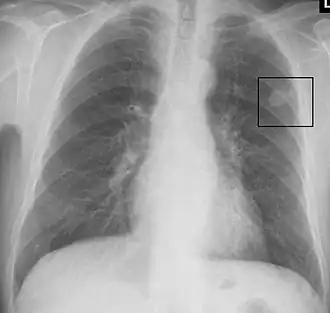

Diagnóstico

Raio-X de tórax mostrando câncer de pulmão no pulmão esquerdo.

A maioria dos cânceres são inicialmente reconhecidos por causa de seus sintomas e sinais ou através de exames. Nenhum dos dois leva a um diagnóstico definitivo, que geralmente requer a opinião de um patologista. Pessoas com suspeita de câncer são investigadas com exames médicos. Estes geralmente incluem exames de sangue, radiografia, tomografia computadorizada, endoscopia, entre outros.[81]